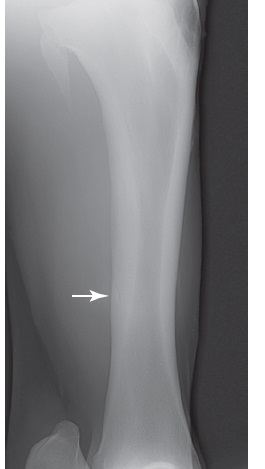

Figure 100-2. A craniolateral-caudomedial oblique radiographic view of a tibia with a midtibial stress fracture. The stress fracture can actually be seen in this horse (arrow), which is unusual because callus normally obscures the fracture.

Figure 100-1. A craniolateral–caudomedial oblique radiographic view of the tibia showing the periosteal and endosteal callus (arrow) that accompanies a caudolateral tibial stress fracture.

Figure 100-3. A craniolateral–caudomedial oblique radiographic view of the proximal tibia, which shows a chronic stress fracture of the proximal caudal tibia with associated callus (arrow).